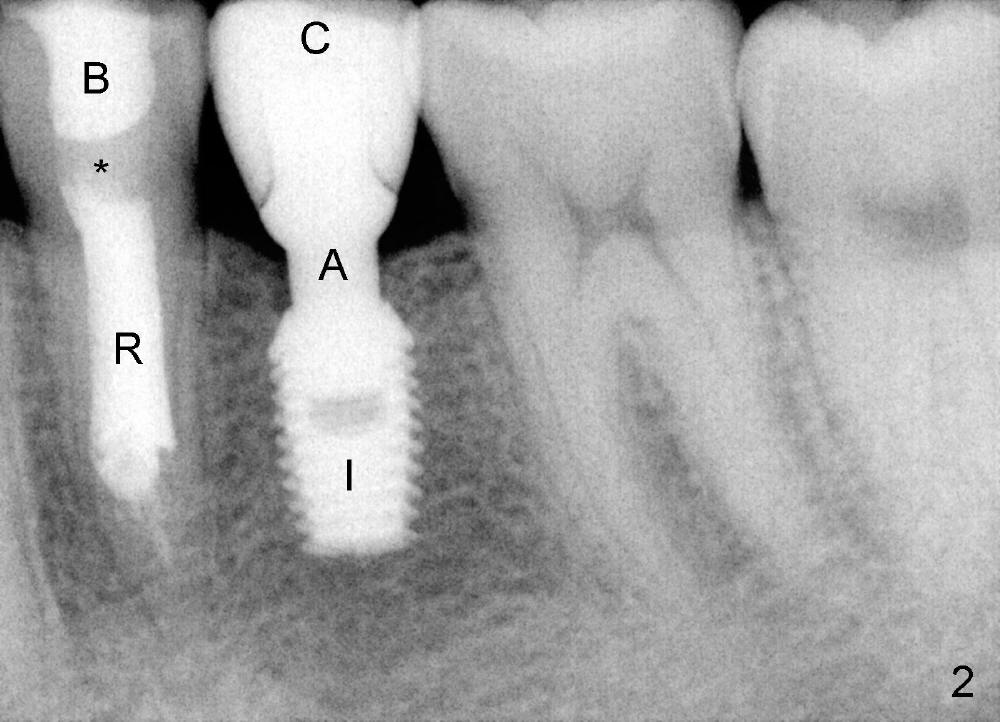

五年前,小许二十出头,四个下颌双尖牙中央牙尖畸形,左下第二双尖牙(图一:5)好像没有症状,但挺难保留,拔除后三个月植牙(delayed vs. immediate,这治疗(delayed implantation)合适吗?),图二是牙冠(C)戴上后半年拍摄的,A:基牙,I:Bicon植牙(5x8 mm,太短吗?)。虽然第一双尖牙也没有症状(图一:4),植牙前,重做根管治疗(图二:R,过分治疗吗?),使用flowable(*)和packabe(B)树脂关闭根管治疗开口,选择不做牙冠(治疗不足?)。